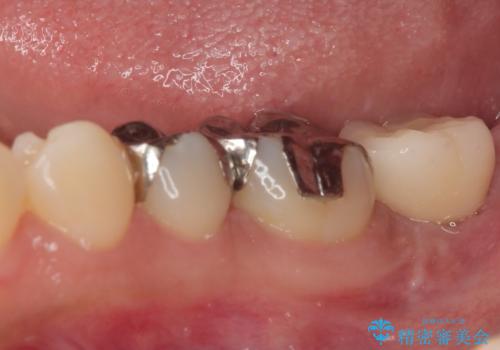

- 奥歯を抜歯してから放置しているとのことで来院された患者様です。

歯が割れて抜歯になってしまったとのことで、咬合力に抵抗できるよう、インプラントによる補綴治療を行うこととしました。

長い期間歯が欠損していた下顎奥歯に、インプラント埋入と同時に仮歯を装着すると(埋入即時荷重インプラントを行うと)、舌の付け根で仮歯を横向きに押してしまい、インプラントが脱落する危険性が高くなります。

インプラント埋入時に、装着できる状態の仮歯を用意するものの、埋入後すぐには加重させず、インプラントが無事に生着したことを確認した後に装着することで、危険を回避しつつ外科処置や痛みの少ないスムーズな治療を行うことができます。